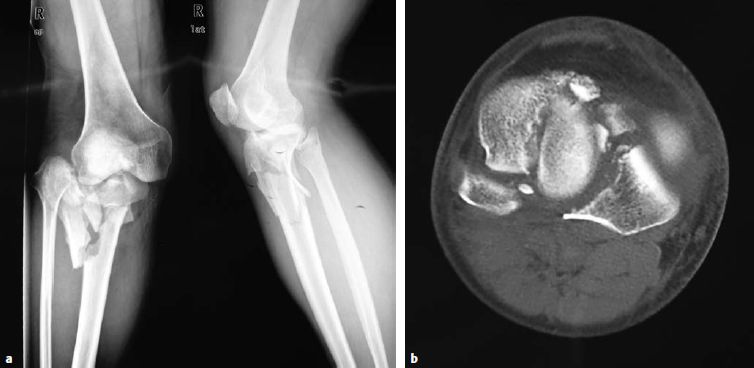

图片图6.8.1-24a-d 胫骨平台双髁骨折一名46岁男性机动车车祸时右腿受伤a  术前X线正、侧位;b  胫骨平台的轴位片;c  骨折的三维重建;d  术后X线正、侧位片

外侧平台骨折随后可以通过前外侧或者髌旁外侧切口来凑上内侧髁(解剖复位)。随后,在实施最终复位和固定前,C型骨折就转化成了一个B型骨折。外侧平台关节面塌陷的复位,处理原则与前述41B3型骨折类似。解剖复位关节面后,在应用钢板前使用拉力螺钉进行固定非常重要,因为干骺端和骨干部分的粉碎可以通过一块长的3.5或4.5mm的锁定钢板进行桥接固定(图6.8.1‑24)。